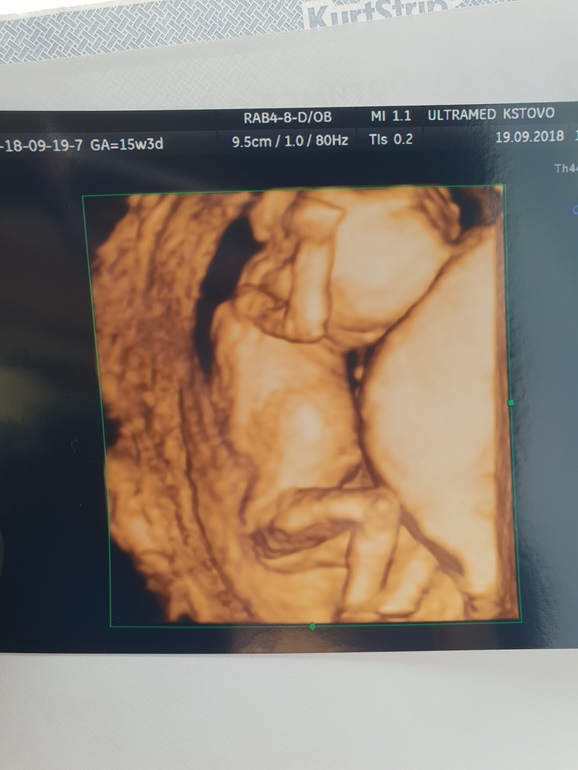

Узи 15-16 недели)

Очень здорово, обожаю фотографии с 3D УЗИ!!!

Такие эти классные фотки 3-дешные!!😍 Пусть будет девочка:)

Да фотки класс)))даже не верится что там уже такой человек)))